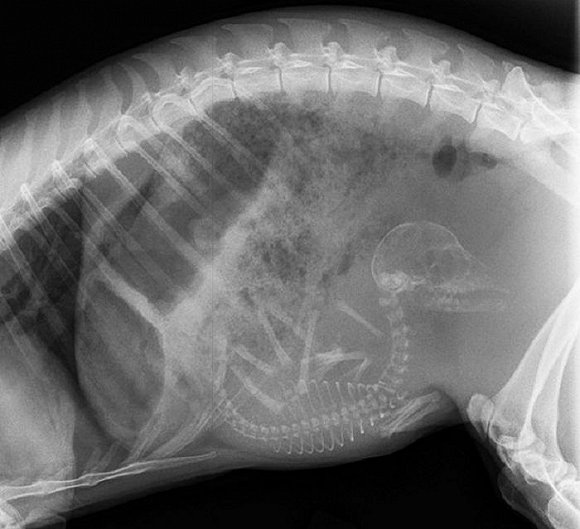

可爱又毛骨悚然 怀孕动物的X光片

人类之间分享母亲肚子里胎儿的X光片是一件非常常见的事情,但是,纵使你觉得自己对X光片已经见怪不怪,在看到了下面这些怀孕动物的X光片后你仍旧会说"哦我的天哪"。

自然总是充满有趣事实,你是否知道在各种怀孕的动物中负鼠的生育速度最快?它们只需要14天就可以分娩,而雌性大象的怀孕时间则长达23个月。现在 吉尼斯世界记录上记载的一次分娩中最大小狗出生数量为24只,而海马的生殖则由雄性负责,一只雄性海马每次平均产出200只幼鱼苗。

以下就是一些动物在怀孕时的X光片。

3. 狗